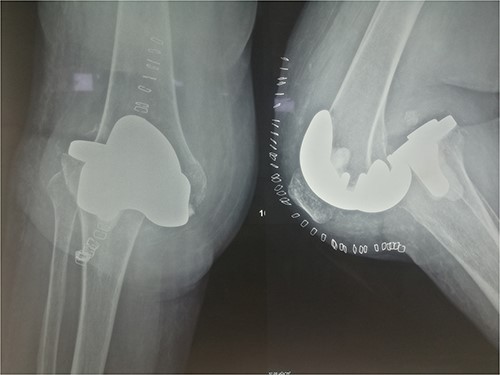

The patient underwent a medial-pivot design TKA (Evolution Medial-Pivot Knee System, Microport, China). Intraoperatively, a full ROM was achieved only after extensive soft tissue and bone releases. The extension gap was limited by significant hamstring spasticity, and a proper extension gap was attained after additional anterior femoral cut. Early postoperative recovery was uneventful (Fig. 2). On the third postoperative day, the patient complained of severe knee pain accompanied by excessive swelling during kinesiotherapy. Clinical examination showed a posterior sag sign at 30° of flexion (Fig. 3). No signs of neurovascular deficit were obvious. A knee X-ray revealed posterior TKA dislocation and a small, non-displaced femoral fracture (Fig. 4). The tibial component was reducible, but redislocation occurred with the knee extended over 90°, indicative of severe instability. Laboratory investigations, including erythrocyte sedimentation rate and C-reactive protein, were normal. A knee arthrocentesis was performed with no substantial findings. Two botulinum toxin injections (200 IU) to the hamstrings were performed without improvement. Local muscle hypertonia was evaluated through a neurological examination and a brain computed tomography scan, with no remarkable findings. The patient’s history included intramedullary nailing of the right femur due to an intertrochanteric fracture 8 months before the TKA.

The patient was reoperated, where a more extensive release of the hamstrings was performed, obtaining full extension. The knee was stabilized using a lateral external fixator (Fig. 5). Muscle biopsies were obtained, indicating signs of chronic inflammation. Full weight bearing, using a walker, was permitted from the first postoperative day without substantial complaints.